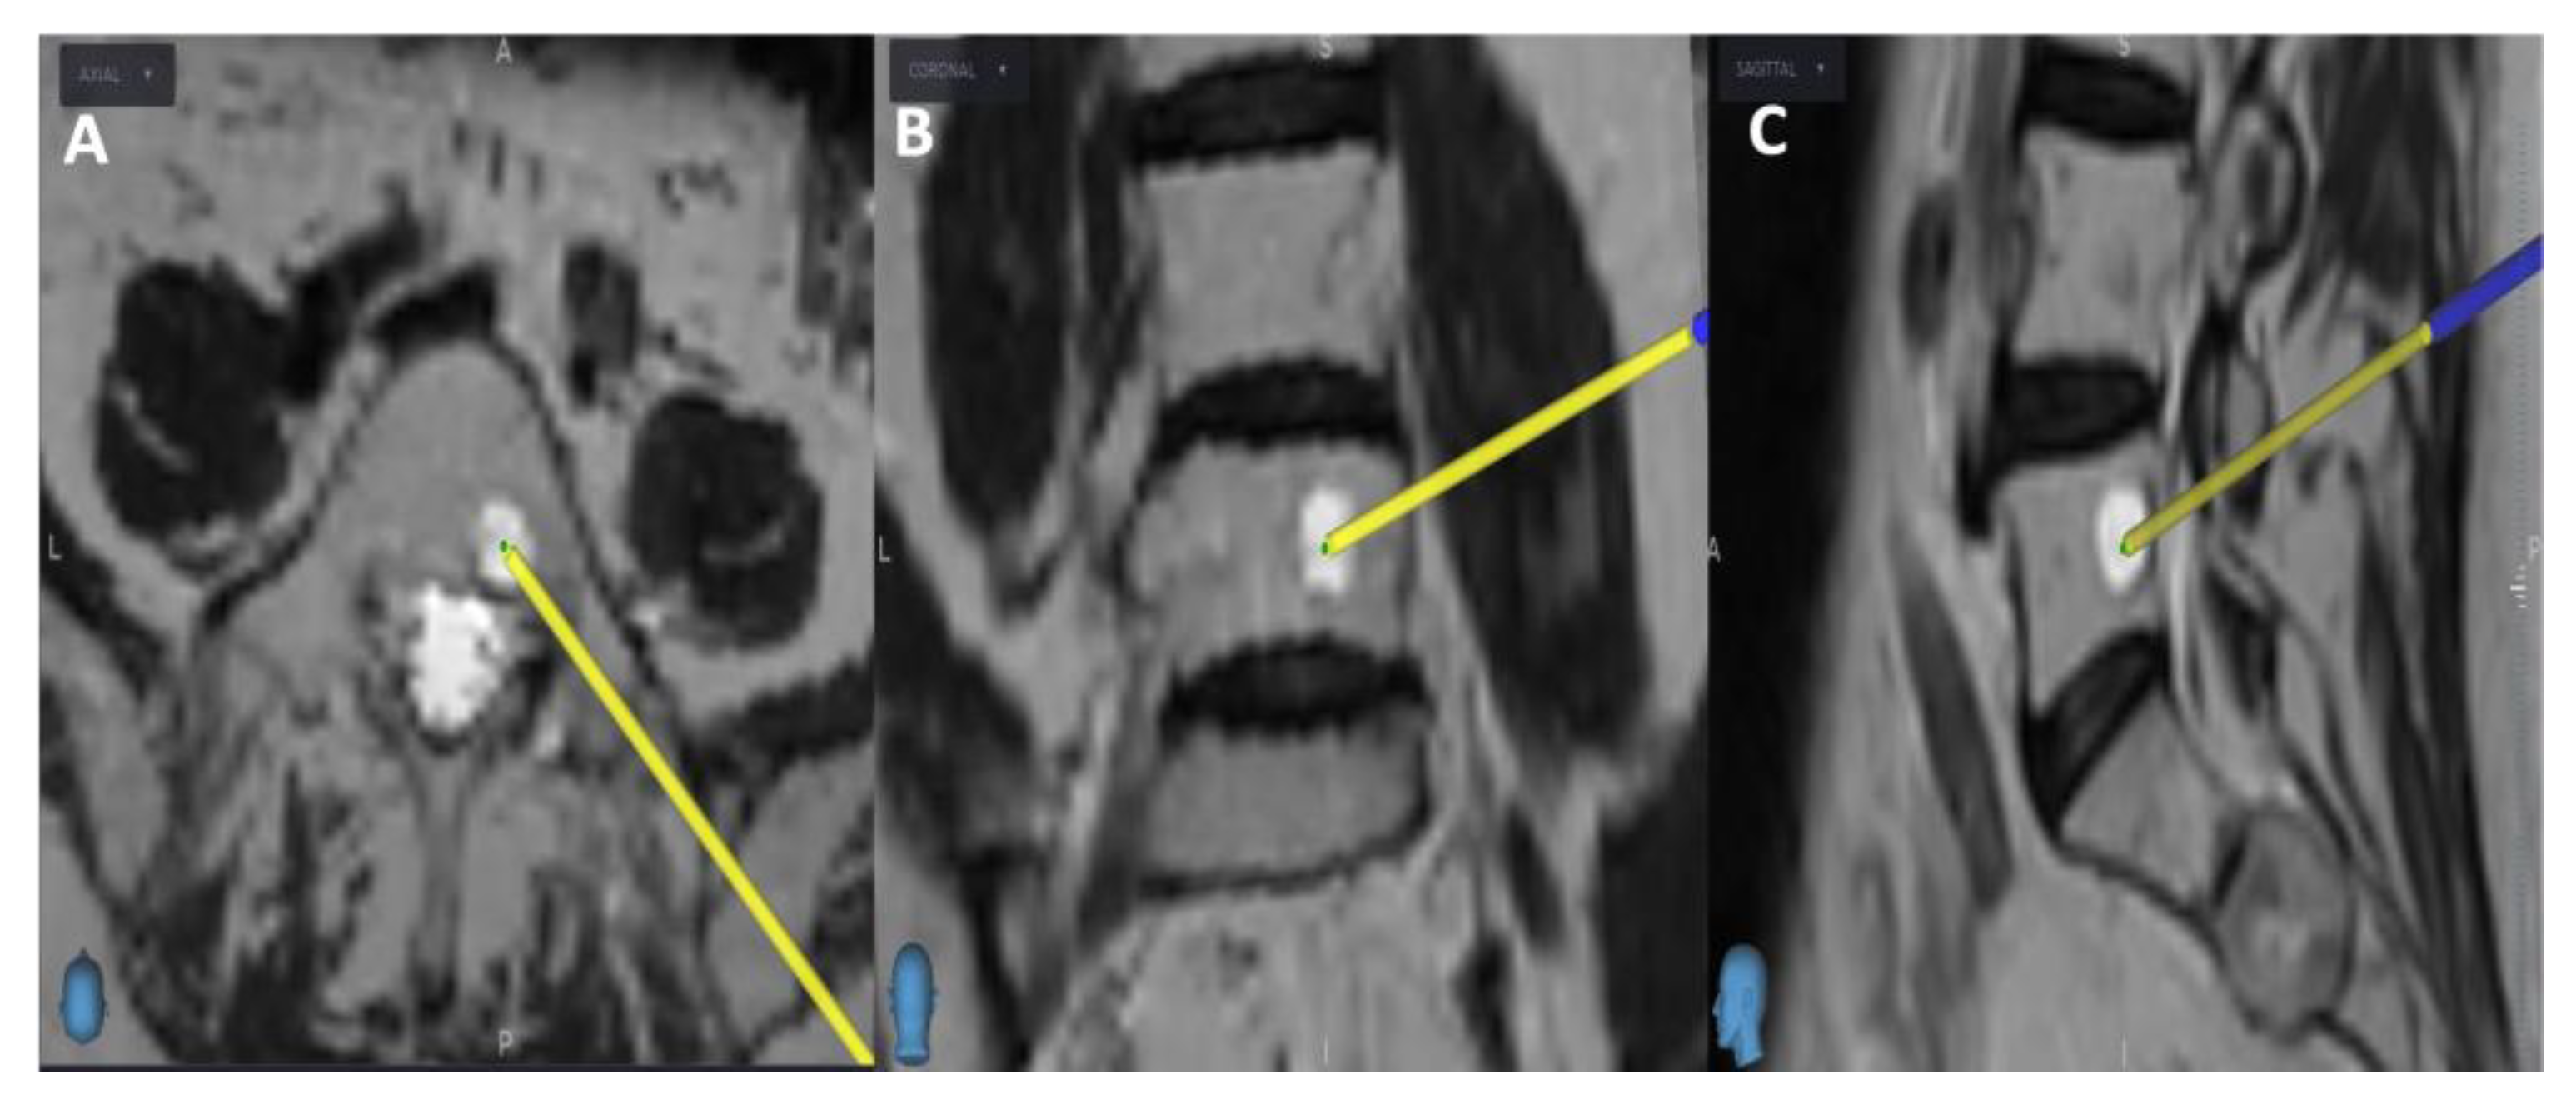

After a 5 mm skin incision, the surgical technique projected on the screen entered the vertebral body and performed a needle biopsy sampling using the Johnson and Johnson 8G vertebroplasty needle. During vertebroplasty sampling, the position of the needle to be inserted was also checked on the O-arm scan, not only on the MRI scan. After the needle biopsy sampling, the O-arm device was returned to the previous O-arm scanning position. Next, an O-arm scan of the same spinal segment was performed, and then the O-arm scan was merged with the needle biopsy plan previously selected in the MRI scan using the "Merge Image" function. If the position of the needle biopsy channel in the second O-arm scan matched the needle biopsy plan selected in the MRI scan, the needle biopsy sampling was considered successful (Figure 3). Finally, the Spine Stealth Air reference frame was removed.

Figure 3. Post-biopsy O-arm and MRI fused image, with A) Axial view, B) Coronal view, and C) Sagittal view. The left half of each view displays the MRI scan. The right half displays the O-arm scan. Red arrows indicate the biopsy sample location.